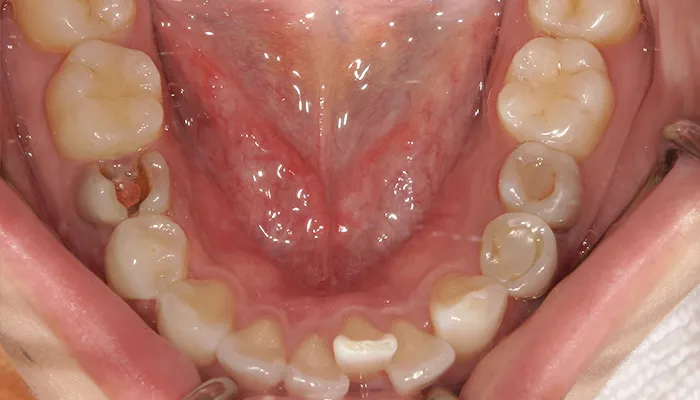

初診時の口腔内写真

術前の口腔内写真

右下5番は大きく崩壊しており、保存不可能な状態でした。

また、下顎前歯部を中心に叢生があり、歯列が不均一でした。咬合関係が不安定で、清掃性も低下していました。

全体的に歯の色もやや黄みを帯びており、患者様からも審美的な改善希望が強くありました。